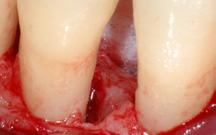

Figure 4.1 : Parodontite à un stade avancé, liée à la présence d’importants dépôts de plaque dentaire et de tartre.

4.1 PARODONTITE (DÉCHAUSSEMENT DENTAIRE) : DE QUOI S’AGIT-IL ?

La parodontite est le terme médical qui désigne le déchaussement dentaire.

La parodontite est une maladie. Elle est due à un déséquilibre entre les bactéries de la plaque dentaire et votre système de défense (système immunitaire) qui cohabite normalement en équilibre.

Dans un premier temps, une inflammation de la gencive s’installe en réponse à la présence de bactéries qui arrivent à passer entre la gencive et la dent et qui se collent sur la racine dentaire. Elles forment alors du tartre sous gingival qui se comporte comme une épine sous la peau. La gencive devient gonflée, rouge et peut saigner au brossage ou même spontanément. Il est important de noter que ces signes sont beaucoup plus discrets chez les fumeurs car le tabac réduit fortement le saignement.

Progressivement, ces bactéries et la mauvaise réponse de votre système immunitaire attaquent l’os qui disparait, laissant apparaitre la racine de la dent, on observe alors un « déchaussement de la dent ».